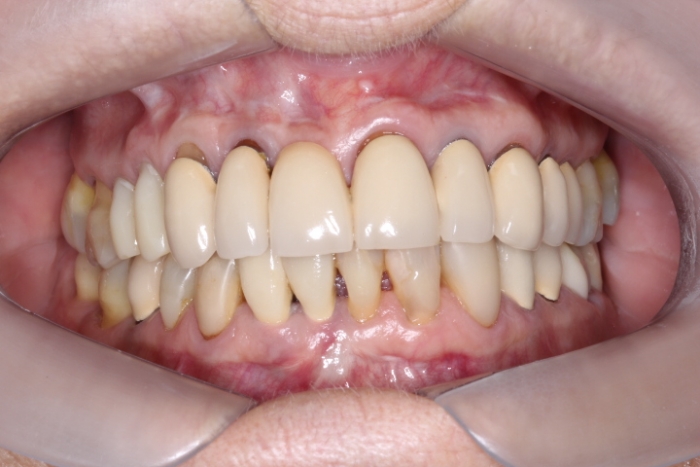

Foto intra oral frontal inicial